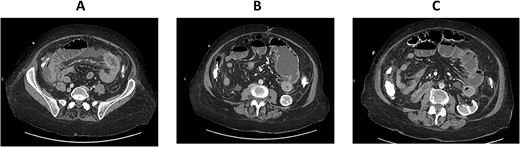

CT enterography: coronal views demonstrating dilatation of the bowel loops in the left lower quadrant associated with bowel thickening and collapsed small bowel loops distally.

The patient is a 71-year-old white female with a past medical history of PSC who underwent orthotopic deceased donor liver transplant in 2006 with a Roux-en-Y hepaticojejunostomy biliary anastomosis. Cholecystectomy was performed to the donor liver. Her course has been complicated over the years by recurrent cholangitis requiring a permanent percutaneous biliary drainage tube. The patient had a liver biopsy in 2011 which showed recurrent PSC, but the patient refused any further liver transplants. Her daily immunosuppressive regimen consisted of cyclosporine 25 mg. Thirteen years after the deceased donor liver transplant, the patient presented to our emergency department with abdominal pain for a week which was associated with abdominal distention and nausea. Her liver function tests and complete blood count were normal on admission. Computed tomography (CT) scan of her abdomen and pelvis with intravenous contrast demonstrated focal dilatation of proximal jejunal bowel loop at the site of anastomosis with air-fluid/debris level (Supplementary Figure 1). She was admitted to the hospital and was initially managed conservatively with nasogastric tube suction, bowel rest and intravenous fluid hydration. A small-bowel follow-through study was obtained which revealed contrast within the colon with no radiographic evidence of bowel obstruction. The patient’s clinical condition improved on her second day after admission and a trial of diet was performed, but the patient had worsening symptoms and subsequently developed peritonitis on her fourth hospital day. CT enterography was obtained which revealed dilatation of the proximal small bowel loops proximal to the small bowel anastomosis in the left mid-abdomen with mild wall thickening of the small bowel in the left lower quadrant without definitive obstructing cause or evidence of pneumatosis (Figs 1A–C and 2A,B). The patient was taken emergently to the operating room for an exploratory laparotomy. The jejunojejunostomy was intact and dilated with dilated proximal Roux limb. Approximately, 50 cm distal to the jejunojejunostomy in the common limb, a firm, round mass was palpated in a segment of bowel which was very edematous, friable, inflamed, with a focus of necrosis without obvious perforation. The remainder of the small bowel was normal. Given the state of the small bowel with the focus of necrosis, the decision was made to perform a small bowel resection with a hand-sewn anastomosis. The resected small bowel was opened off the field, and an impacted bezoar was found with small circular yellowish objects thought to possibly be gallstones mixed with other fibrous content. The resected small bowel pathology showed focal mucosal ulceration, transmural hemorrhage and acute serositis. The patient had an uneventful post-operative course and was discharged home 7 days after surgery. She was seen in clinic for a follow-up appointment a month after the surgery and was found to be doing great, tolerating her diet and having regular bowel function.